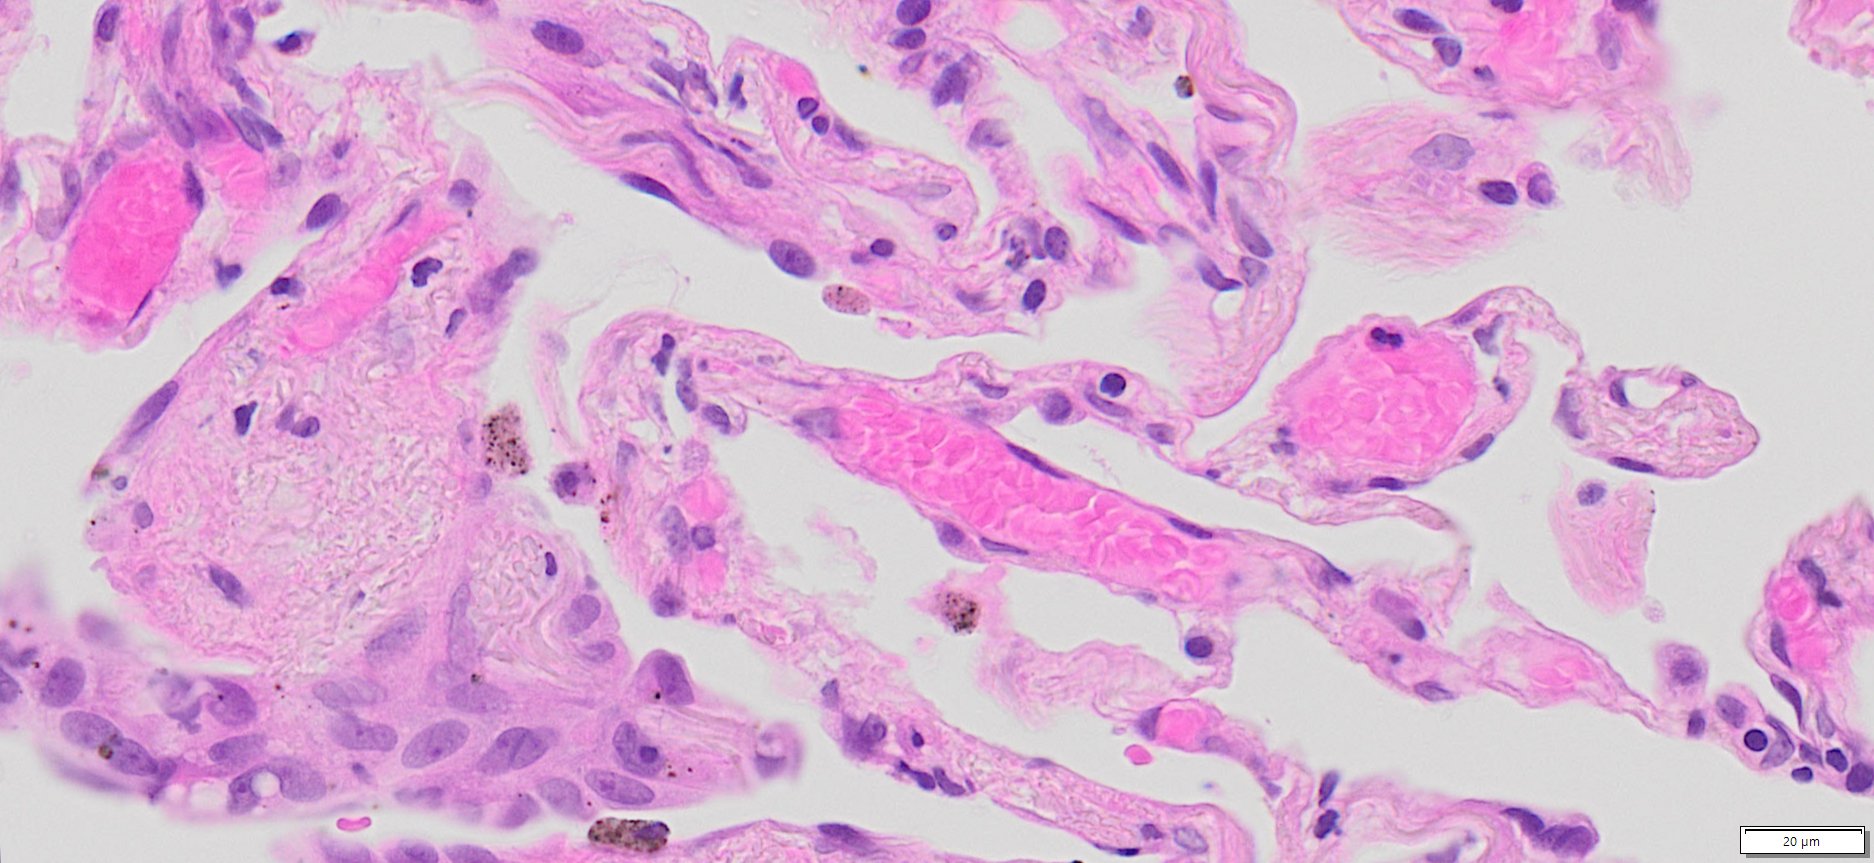

Description

| SKU# | Organ | Pathology Diagnosis | Gender | Age | Grade | TMN | Thickness | IHC Data |

| HuPS-03003A | Human Lung | Lung cancer adjacent normal tissue | Male | 51 | — | — | 5 μm |

Human tissue was fixed in formalin immediately after excision and embedded in paraffin. The tissue sections were 5 µm in thickness and mounted each on positively charged glass slides.